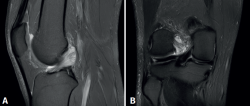

No se evidenciaron alteraciones significativas en el estudio radiológico simple realizado. En la RM se evidenció la presencia de un ganglión del LCA con afectación de su fascículo posterolateral (Figura 1).

Figura 1. Imagen de resonancia magnética del quiste sinovial localizado en el ligamento cruzado anterior. A: secuencia PDW SPIR en corte sagital de la rodilla; B: secuencia PDW SPIR en corte coronal de la rodilla.